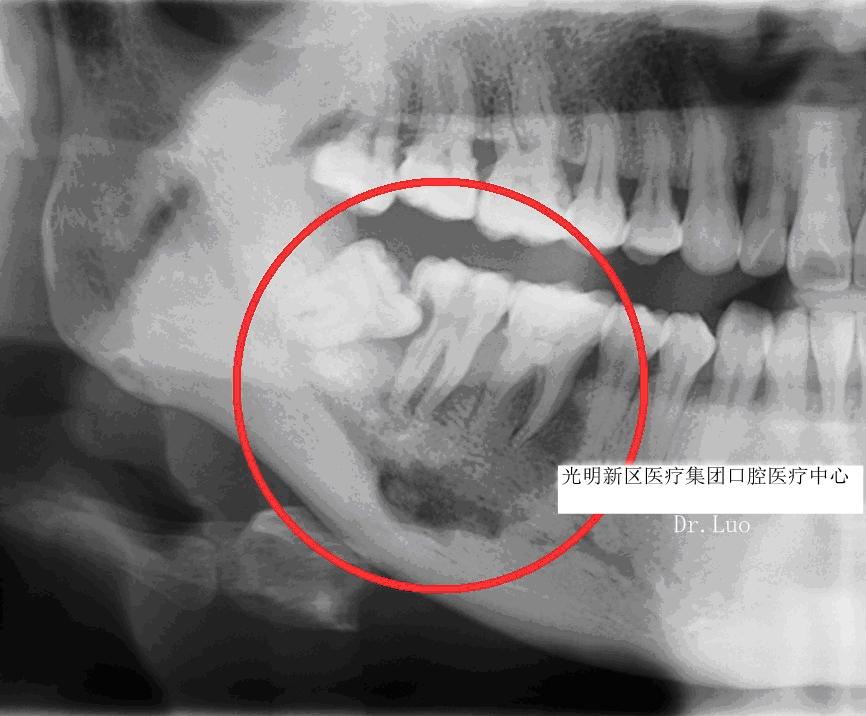

4)根、骨吸收:

由于智齿生长持续的压力压迫,造成邻近牙齿、骨质的吸收。可导致邻牙不适、疼痛甚至松动脱落。

5)牙源性囊肿、肿瘤:

长期的炎症、压迫周围组织可能导致颌骨囊肿、牙源性肿瘤的产生。不仅可能造成邻牙的松动脱落,还可能引起下颌神经的损伤、颌骨的病理性骨折,甚至有肿瘤后癌变的可能。